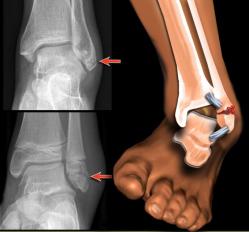

Fratura do Tornozelo

No tornozelo, existem duas protuberâncias ósseas, chamadas maléolos, que são as extremidades distais dos dois ossos da perna, a fíbula e a tíbia. Quando um ou os dois ossos são fraturados, considera-se fratura de tornozelo.

Como é diagnosticada?

Radiografias devem ser solicitadas. Vários ângulos diferentes podem ser radiografados, para localizar com precisão o local da fratura.